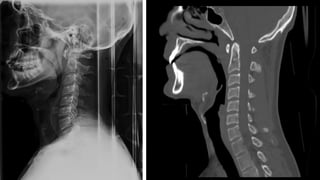

COLUMNA CERVICAL

• Una serie adecuada incluye:

• Proyección lateral de columnacervical con

rayo horizontal

• Deben visualizarse:

• Base de cráneo

• 7 vértebras cervicales.Valorar tracción de

hombros.

• 1ª vértebra torácica si es posible

• AP

• Proyección de odontoidescon boca abierta

• Sin movilizar al paciente

INDICACIONESDE TC Y RM.

• TC:

• Valoración de lesiones complejas o dudosas.

• Detección de esquirlas óseas en el canal raquídeo.

• Si hay indicaciónurgente de TC (politrauma) no hacer Rx

simples.

• RM:

• Afectación del canal.

• Síntomas neurológicos.

• Lesiones ligamentosas.

PARTES BLANDAS

• Valorar hematoma por FX

valorar espacios:

• E. Nasofaríngeo (C1)=10mm

• E. Retrofaríngeo (C2-C4)= 5-7mm

• Retrotraqueal (C5-C7)= 22mm ó

(< 1 cuerpo vertebral).